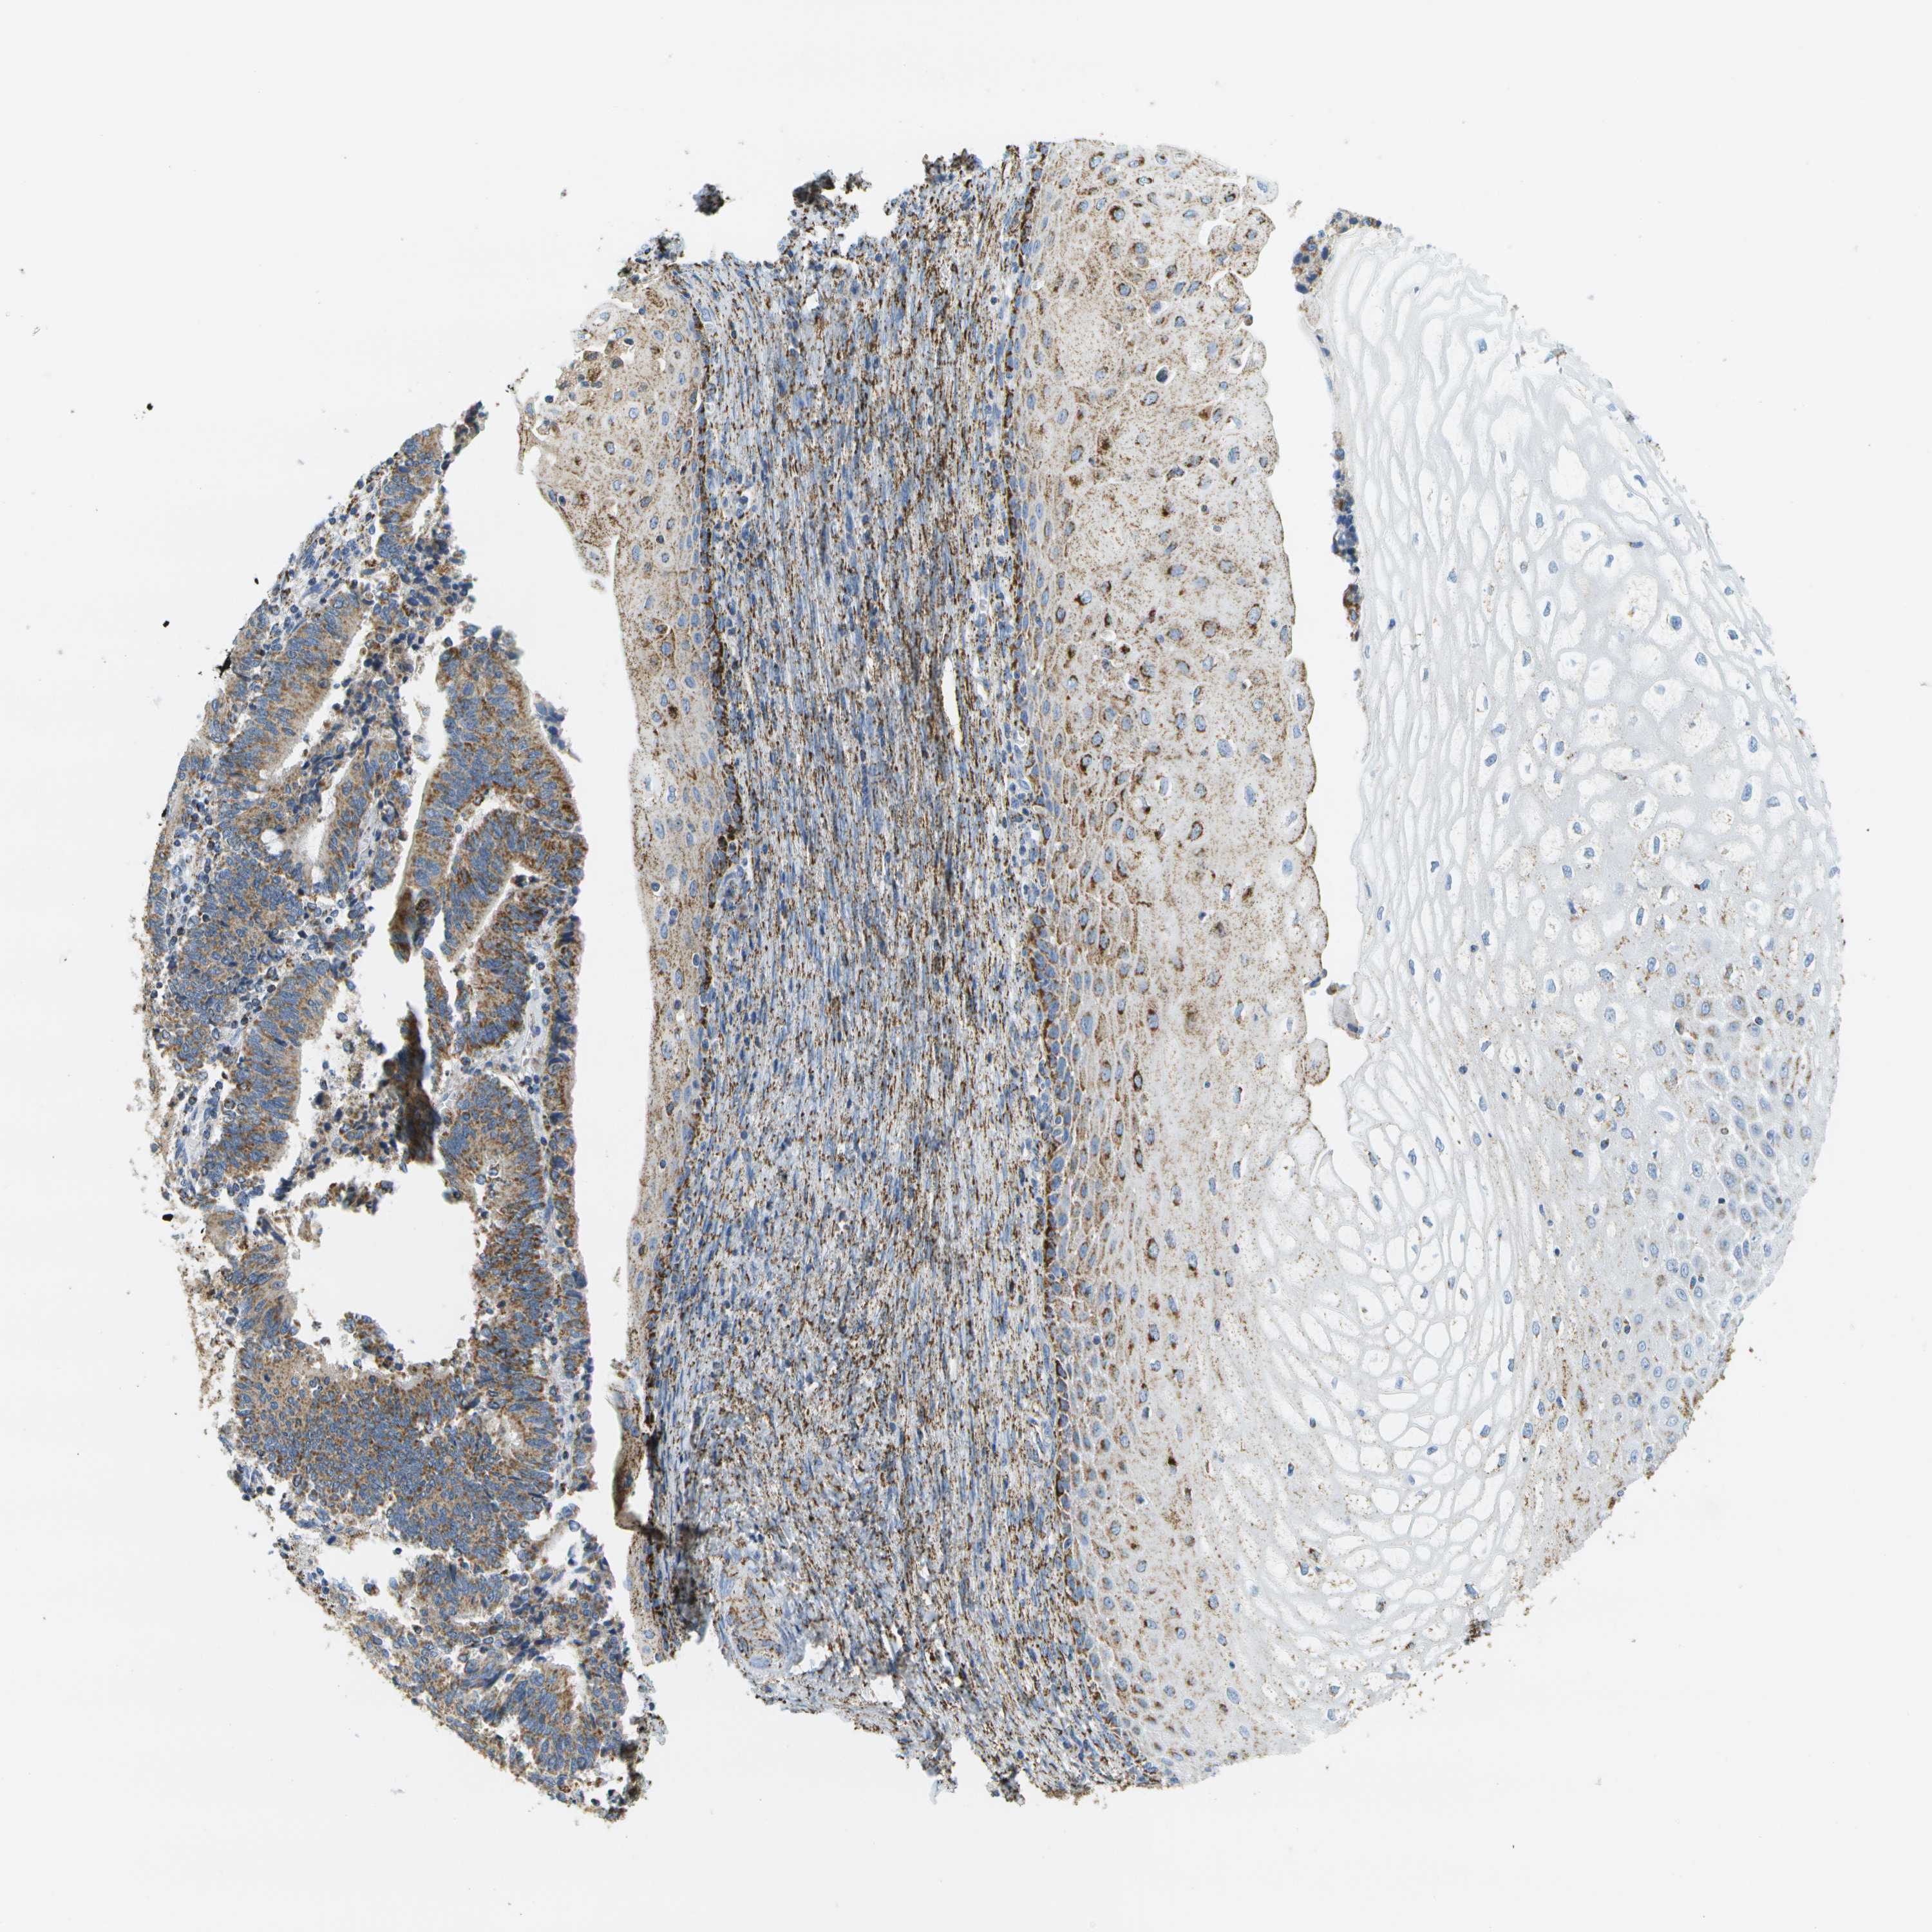

CERVICAL CANCER - Protein expressioni

A mouse-over function shows sample information and annotation data. Click on an image to view it in a full screen mode. Samples can be filtered based on level of antibody staining by selecting one or several of the following categories: high, medium, low and not detected. The assay and annotation is described here.

Note that samples used for immunohistochemistry by the Human Protein Atlas do not correspond to samples in the TCGA dataset.

Antibody stainingi

Antibody staining in the annotated cell types in the current human tissue is reported as not detected, low, medium, or high, based on conventional immunohistochemistry profiling in selected tissues. This score is based on the combination of the staining intensity and fraction of stained cells.

Each image is clickable and will lead to virtual microscopy that enables deeper exploration of all samples and also displays staining intensity scores, fraction scores and subcellular localization as well as patient and tissue information for each sample.

Antibody HPA017379

Staining

High

Medium

Low

Not detected

Intensity

Strong

Moderate

Weak

Negative

Quantity

>75%

75%-25%

<25%

None

Location

Nuclear

Cytoplasmic/membranous

Cytoplasmic/membranous,nuclear

Squamous cell carcinoma, NOS

Adenocarcinoma, NOS